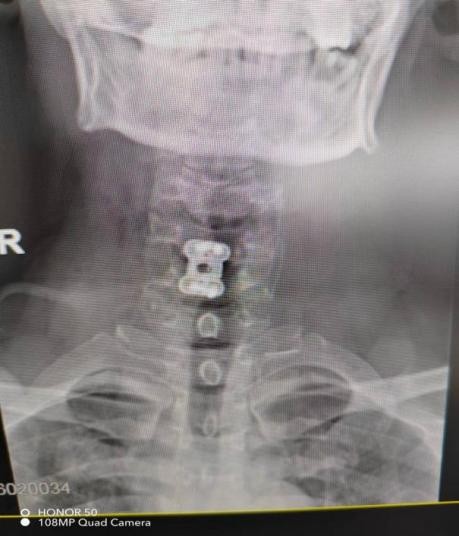

近期,年轻的阿明突然出现一侧肢体无力,开始家人以为“脑中风”,后明确原来为颈椎病椎间盘急性脱出,在广东省人民医院(下称“省人医”)帮扶下,我院骨科予以手术治疗,效果良好,手术后3天顺利出院,患者及家属对医生表示了由衷的感谢!